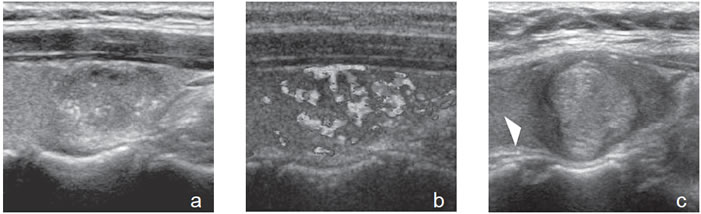

5. Calcificaciones

Pueden ser detectadas en aproximadamente un 10% a 15% de todos los nódulos tiroideos, pero lo más importante es el tipo y patrón de calcificación para distinguir lesiones malignas de lesiones benignas. Se clasifican en microcalcificaciones, calcificaciones gruesas y calcificaciones periféricas.

Las microcalcificaciones aparecen en la ecografía como focos ecogénicos puntiformes, sin sombra acústica y sin artefacto por reverberación, en el espesor del tejido sólido (Figura 8a). Desde el punto de vista histológico corresponden a conglomerados de cuerpos de psammoma, que son esférulas microscópicas laminarmente calcificadas. Se originan a partir de células necróticas, a menudo en las puntas de las papilas, que forman el nido sobre el cual se depositan las láminas de calcio. Se encuentran principalmente en carcinomas papilares (29% a 59%), pero pueden estar presentes en carcinomas medulares y anaplásticos11,16.

Las macrocalcificaciones aparecen como placas ecogénicas fragmentadas, o depósitos granulares amorfos que determinan sombra acústica hacia los planos profundos (Figura 8b). Patológicamente corresponden a calcificaciones distróficas secundarias a necrosis y fibrosis. La distribución puede ser central o periférica y ocurrir tanto en nódulos malignos como nódulos benignos de larga data. En el cáncer papilar pueden coexistir microcalcificaciones con calcificaciones gruesas, que se depositan en áreas de fibrosis y degeneración; las calcificaciones granulares centrales son el tipo más frecuente en el cáncer medular.

El patrón de calcificación periférica anular se consideró alguna vez que representaba un hallazgo benigno, pero un estudio demostró asociación con malignidad en 18,5% de los casos17. En ese estudio hubo una tendencia hacia un mayor riesgo de malignidad si el patrón periférico de calcificación era discontinuo (Figura 9) y un menor riesgo de malignidad si el patrón periférico de calcificación era liso y curvilíneo, en forma de cáscara de huevo (Figura 10).

De todos los signos ecográficos asociados a malignidad, las microcalcificaciones es el más específico (85-95%). La presencia de microcalcificaciones en un nódulo predominantemente sólido aumenta el riesgo de cáncer en tres veces y la presencia de calcificaciones gruesas aumenta el riesgo de cáncer en dos veces. El valor predictivo de las microcalcificaciones varía entre 42% a 94% y la sensibilidad entre 26% a 59%5.